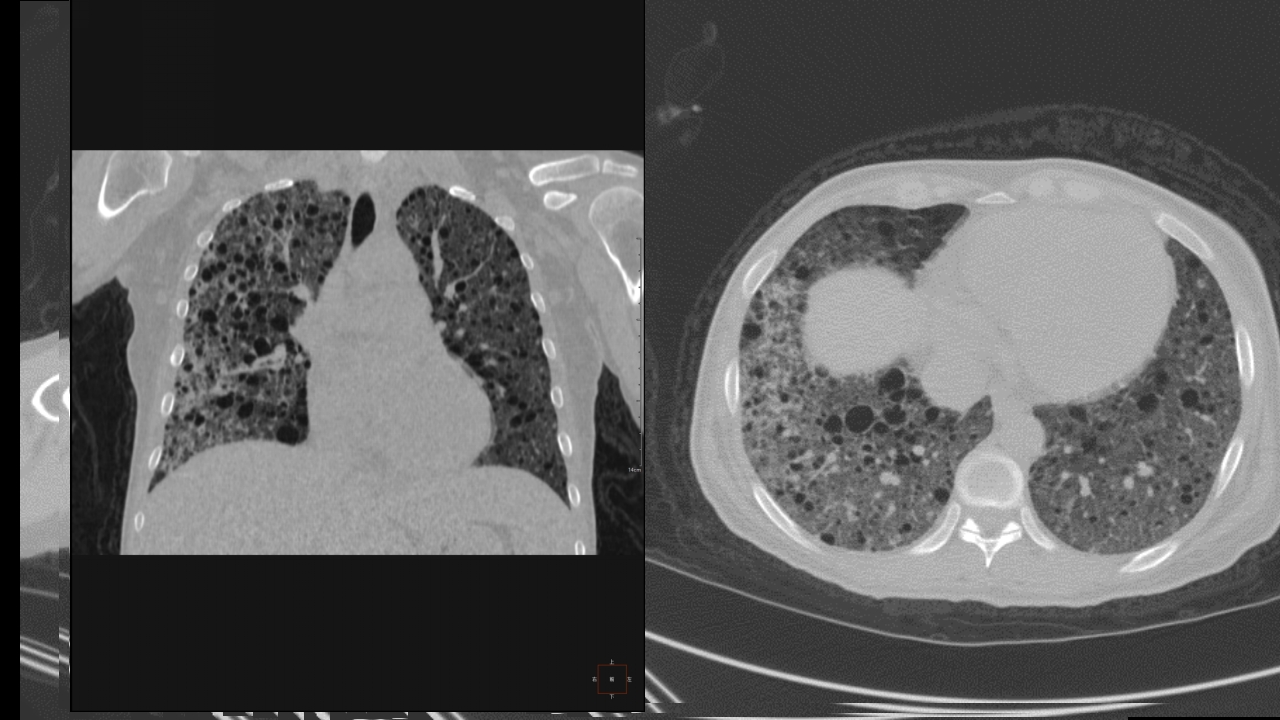

肺淋巴管肌瘤病合并双侧巨大肾血管平滑肌脂肪瘤(X线、CT、MR)